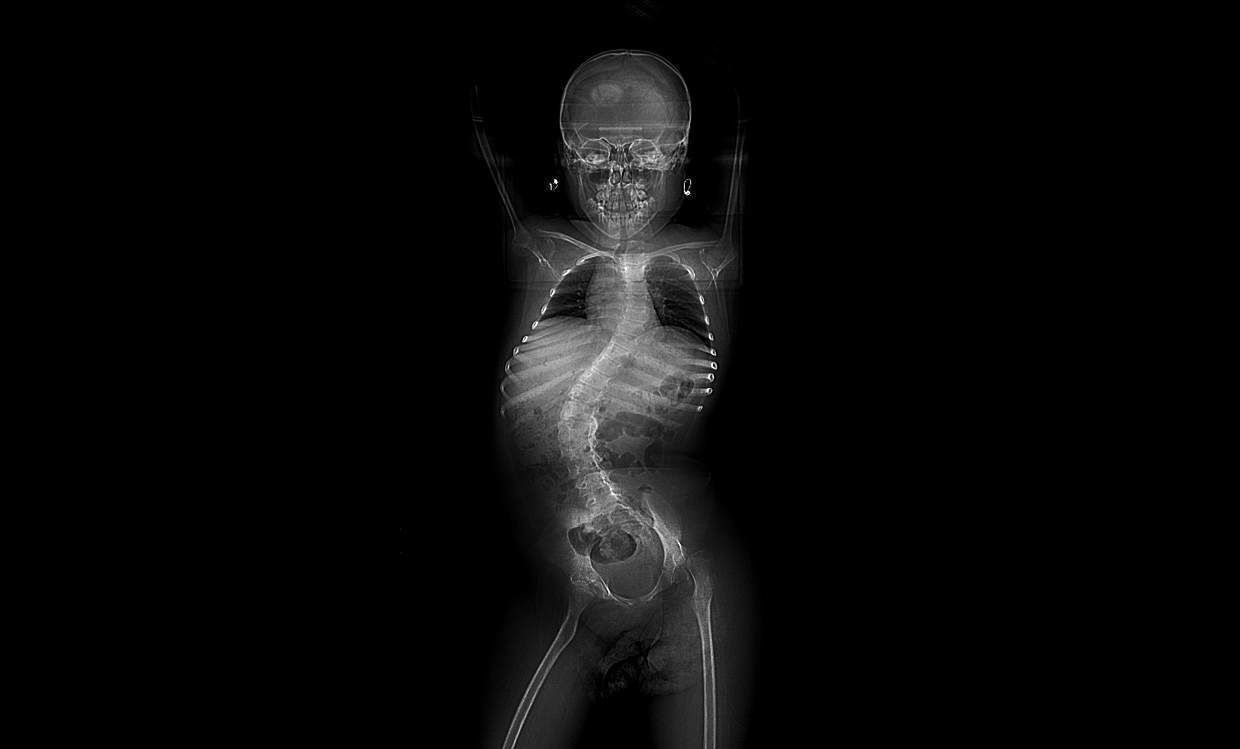

Das von Burnei montierte Shilla-Implantat

Das Shilla-Implantat besteht aus zwei Stangen, die mit Schrauben an der Wirbelsäule befestigt werden. Ein Arzt aus Arkansas hat es sich patentieren lassen. Zum Zeitpunkt von Andreeas Operation hatten es nur eine Handvoll Ärzte aus Großbritannien und Polen eingesetzt. In den USA war es noch nicht zugelassen. Der Vorteil gegenüber bestehenden Implantaten ist, dass keine nachfolgenden Operationen nötig sind, da es zusammen mit der Wirbelsäule wächst.

Allerdings bestätigten uns mehrere medizinische Quellen, dass das Implantat nicht für Patienten mit spinaler Muskelatrophie geeignet ist. Shilla hätte nur die Wirbelsäule des Mädchens betroffen, während ihr Becken gekippt geblieben wäre und sich aufgrund des neuromuskulären Zustands nicht hätte aufrichten können. Das Implantat war deswegen nutzlos.

Ich zeigte Andreeas Röntgenbilder dem auf Wirbelsäulen-Operationen spezialisierten Kinder-Orthopäden Alexandru Thiery und fragte ihn, was in ihrem Fall die geeignete Therapie wäre. „Ich hätte gewartet, bis Andreea zehn Jahre alt ist. Dann wäre bei ihr eine herkömmliche Wirbelsäulenversteifung möglich gewesen”, sagt Thiery. Zur Verringerung der Skoliose des Mädchens hätte es noch andere Möglichkeiten gegeben: „Dual Growing Rod” ist derzeit eine Standard-Technik.